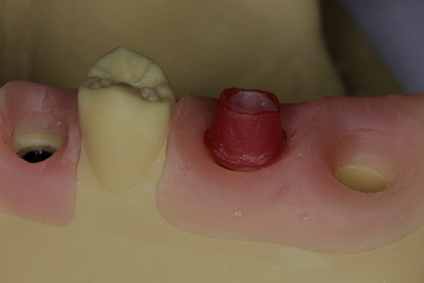

A partir das características descritas acima sobre os pilares UCLA, vamos ilustrar uma sequência para o uso dos pilares do tipo UCLA, lembrando-se que podemos utilizar nas conexões de HE, HI e CM disponibilizadas pela empresa e de acordo com a preferência de cada profissional:

– seguem o fluxo analógico de moldagem tradicional, envio do componente calcinável (UCLA) ao laboratório para enceramento e fundição, com posterior confecção de uma coroa metalocerâmica;

– atendimento mais agilizado, considerando que faremos apenas a remoção do cicatrizador, instalação do transferente na cabeça do implante e moldagem analógica sem a necessidade de escolha de pilar específico e confecção de restauração provisório, otimizando o atendimento clínico;